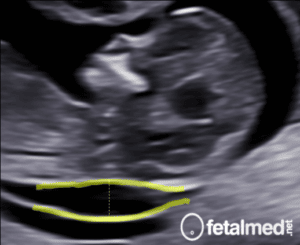

As mãos fetais são examinadas durante o exame morfológico, durante o exame as seguintes anomalias das mãos podem ser observadas no ultrassom:

Mão em garra (clenched hand) – o indicador se sobrepõe a um punho fechado formado pelos outros dedos. A articulação interfalangeana proximal do indicador é flexionada e desviada para o lado ulnar. O polegar é aduzido. Esta posição é constante durante o exame e é fortemente sugestiva de trissomia do cromossomo 18 (Síndrome de Edwards).